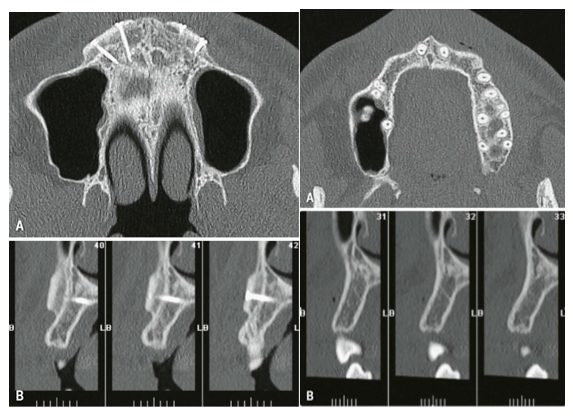

CT示OBG术前术后。图源自引文1

(CT示OBG修复后。图源自引文1)